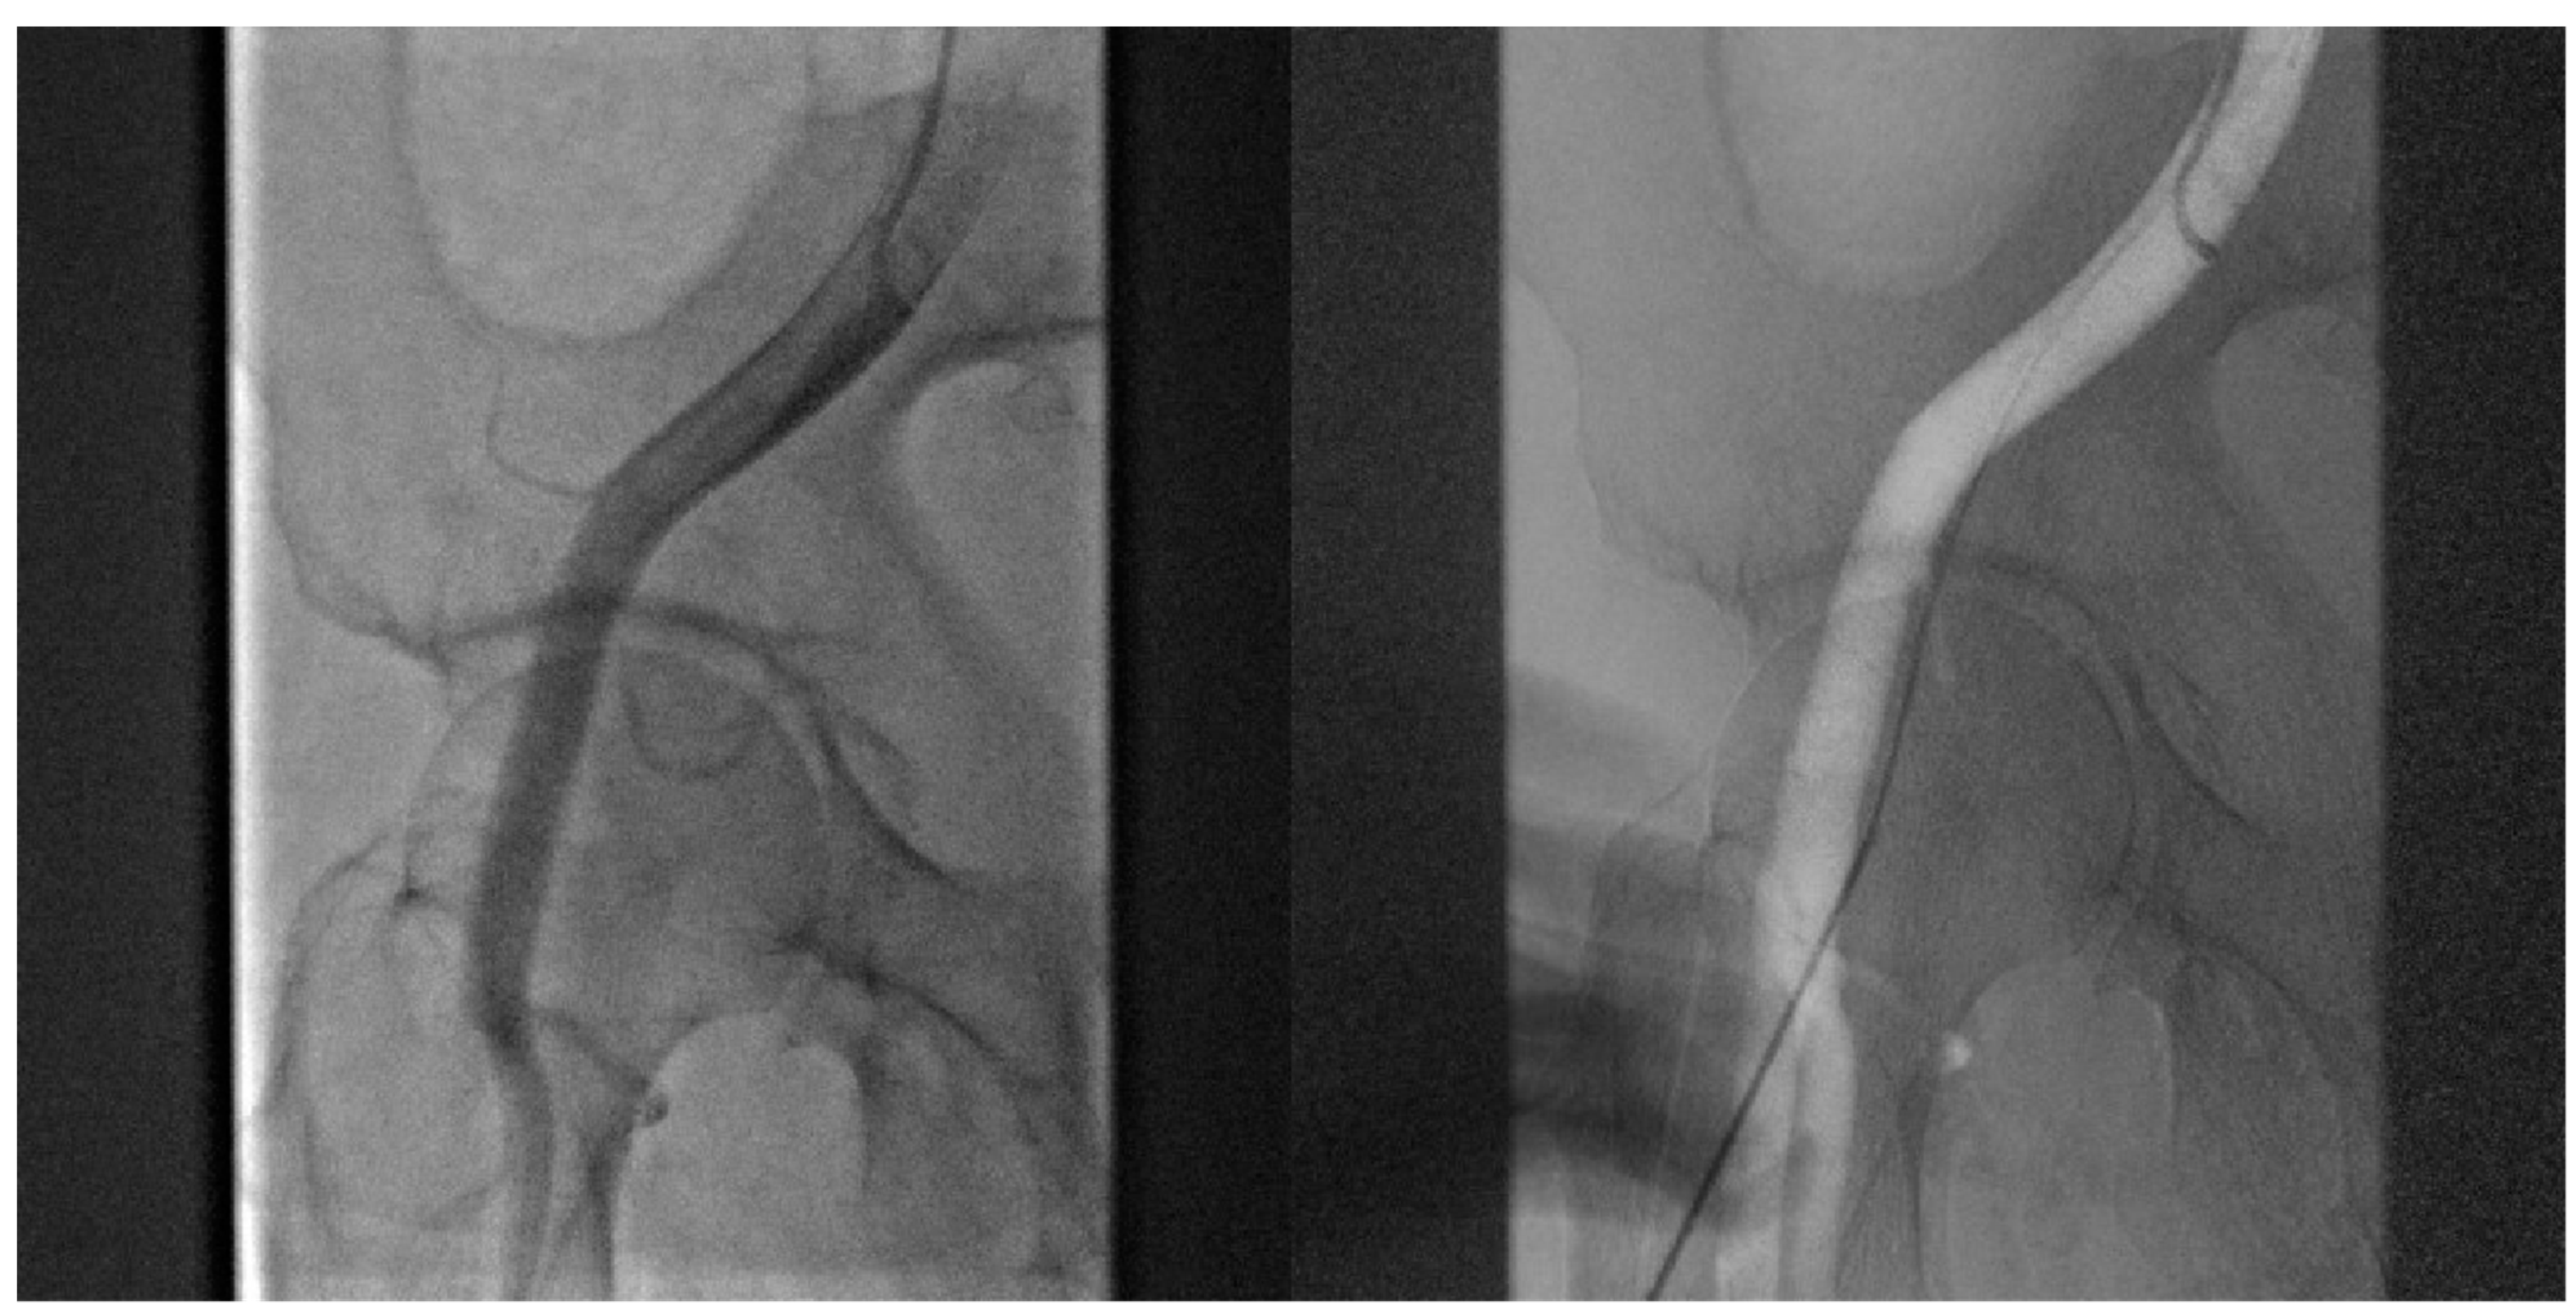

- Angiography-guided femoral puncture: A secondary access is necessary (radial or femoral) for the possibility of reaching the proximal part of the CFA to perform digital subtraction angiography (DSA) and road mapping Figure 3 to guide the puncture.

- Cardiogenic shock pre-PPCI: Time is muscle. After basal coronary angiography, in order to place a pMCS the use of DSA would probably be the faster option Figure 8.Digital subtraction angiography could be obtained using the index access (radial access or CFA contralateral). From this angiography it is possible to obtain information related to the bifurcation site, such as stenosis of the femoral axis. With the use of road mapping it is possible to perform a safe and correct puncture.In case of severe disease of the femoral route, the only option is IABP (with a minimum diameter of 3 mm) or a primary PCI without support (in case of obstructive disease of the femoral axis).If the femoral route is feasible in patients older then 70 y, IABP is the best option, with subsequent hemostasis with manual compression (after ACT evaluation) sometime after the index procedure.If the patient is younger than 70 y, Impella CP seems to be the best option to manage the instability situation.The puncture should be performed with DSA road mapping, ultrasound or micropuncture.Management of vascular access is crucial in this setting, and is it possible to achieve the best hemostasis using 2 Proglide, 1 Proglide and 1 AngioSeal or Manta.